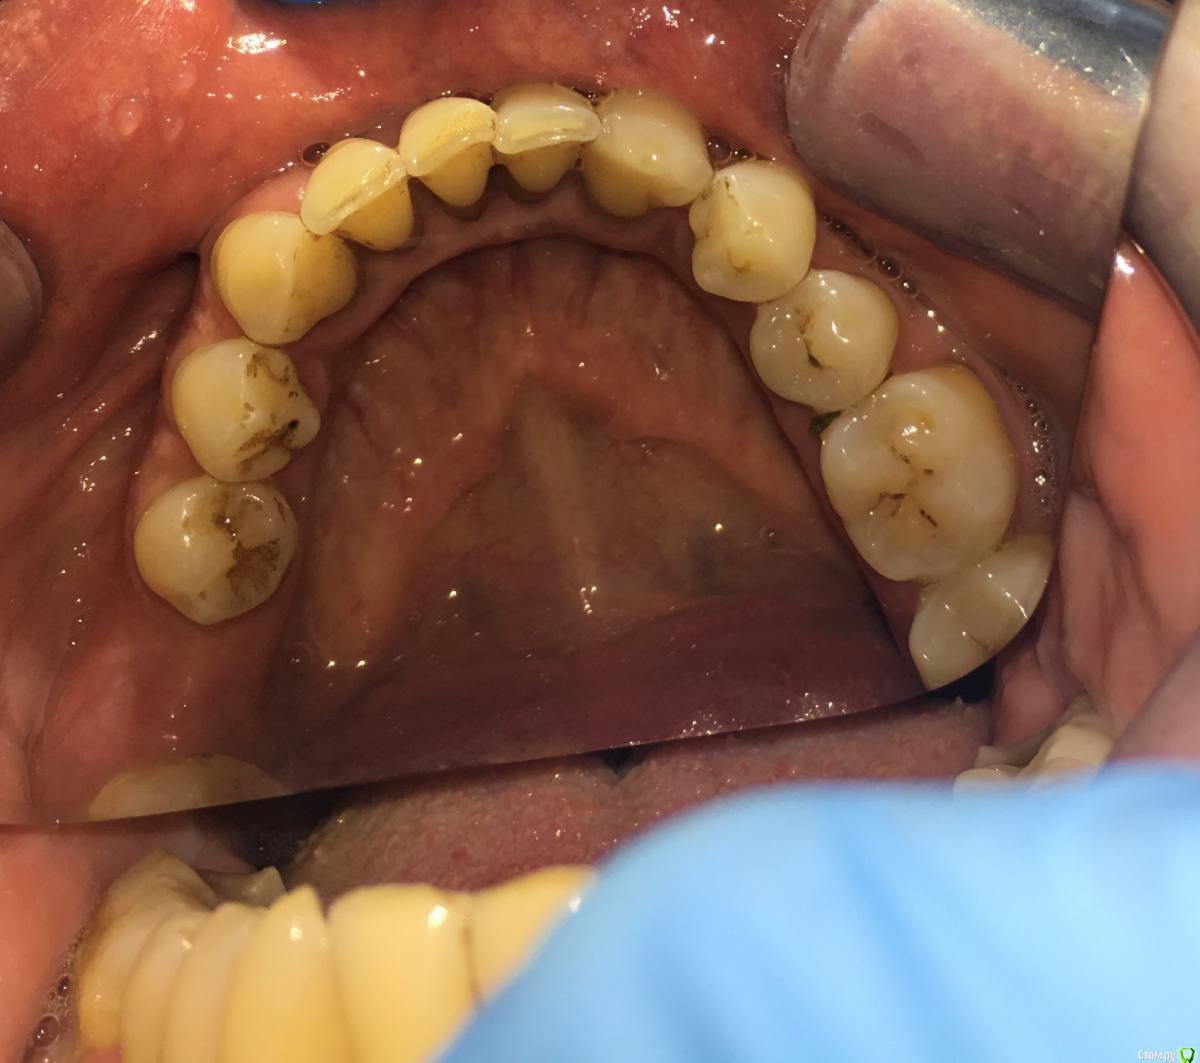

Nitrino1 Опубликовано 20 января, 2018 Поделиться Опубликовано 20 января, 2018 Коллеги помогите поставить правильный диагноз и составить план лечения, чтоб продолжительно держалосьОбъективно на всех зубах камни над и поддесневые. В 47ом зубе 3-я степень подвижность.Почистил все камни и налеты, назначил полоскание, пасту Парадонтах, удалил 47ой зуб.Сделал панорамку (до удаления) и фотки тоже до удаления.Должен составить план лечения... Ссылка на комментарий

red_butler Опубликовано 21 января, 2018 Поделиться Опубликовано 21 января, 2018 Хронический генерализованный пародонтит тяжелой степени, в ремиссии (по МКБ-10 Хронический генерализованный пародонтит, код К0531) Ссылка на комментарий

Nitrino1 Опубликовано 21 января, 2018 Автор Поделиться Опубликовано 21 января, 2018 Хронический генерализованный пародонтит тяжелой степени, в ремиссии (по МКБ-10 Хронический генерализованный пародонтит, код К0531)какой план лечения вы бы порекомендовали? интересует момент с нижними резцами, их шинировать или же удалить? на верхних 6ках тоже ситуация не очень. Вообще какую тактику выбрали бы?И еще просьба, посоветуйте что можно почитать современное на тему парадонтитов и парадонтозов, то что у меня есть это старое уже Ссылка на комментарий